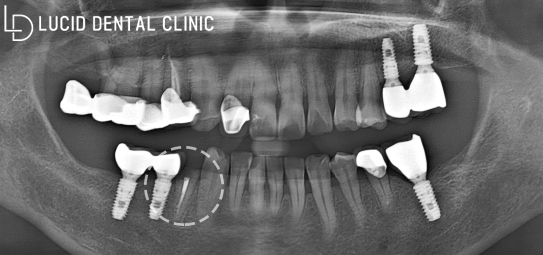

이미 여러 수복을 받은 것으로 보아

구강 관리 능력이 미흡하다는

사실을 추측할 수 있었는데요

여기 화살표로 표시한 곳을 보면

근관 수복된 치아 머리 부분이

부러져 있는 걸 알 수 있었습니다.